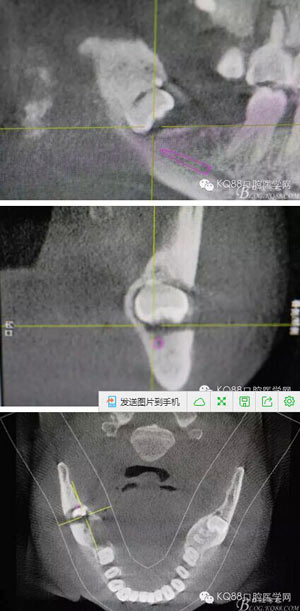

圖2.術(shù)前的CBC影像T檢查:48低位導(dǎo)致,近中牙尖緊鄰下頜神經(jīng)管。

2.jpg

圖3.其他方向的影像檢查:48近中牙冠與下頜管之間無骨壁相隔。

3.jpg

圖4.總體的CBCT影像:

4.jpg